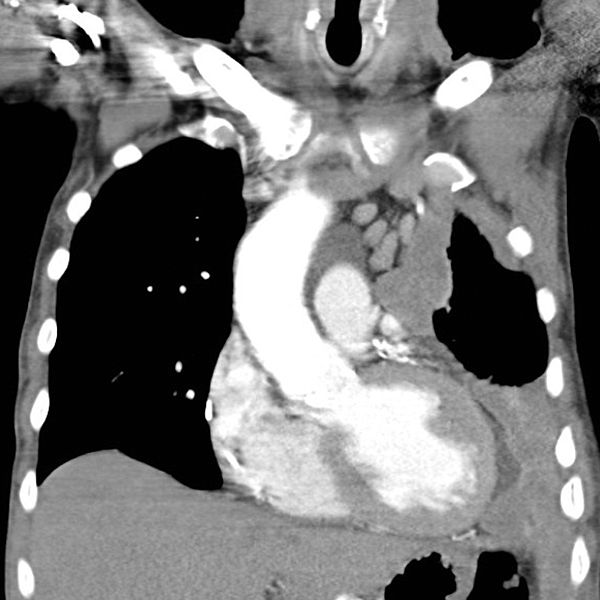

600px-MesotheliomaCTRadyolojik bulgular: Direkt grafide; efüzyon, diffüz plevral kalınlaşma, nodüler yapı görülebilir.

Toraks BT: evreleme ve cerrahi öncesi değerlendirme için gereklidir. Hidropnömotoraks (%73), ilgili hemitoraksda volum kaybı (%73), plevral kalınlaşma (%93), nodüler veya lobüler plevral kitle (%52), kalsifik plevral diafragmatik plaklar veya fibröz plaklar (%62), kosta destruksiyonu (%16), yumuşak doku invazyonu, parankimal fibrozis, kardiyomegali, perikardiyal efüzyon, lenfanjitik yayılım ile uyumlu görünüm, interlober fissür kalınlaşması veya nodüler görünüm (%76), mediastinal genişleme veya düzensiz mediastinal kontur görülebilir.